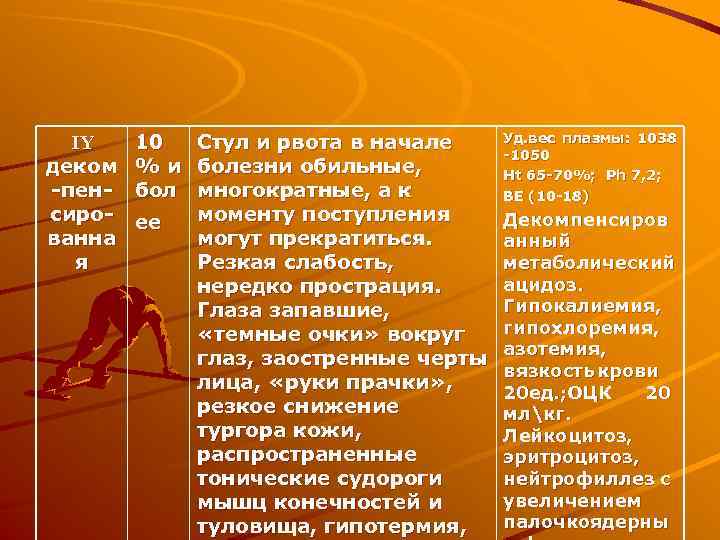

IY деком -пенсированна я 10 Стул и рвота в начале % и болезни обильные, бол многократные, а к моменту поступления ее могут прекратиться. Резкая слабость, нередко прострация. Глаза запавшие, «темные очки» вокруг глаз, заостренные черты лица, «руки прачки» , резкое снижение тургора кожи, распространенные тонические судороги мышц конечностей и туловища, гипотермия, Уд. вес плазмы: 1038 -1050 Нt 65 -70%; Рh 7, 2; BE (10 -18) Декомпенсиров анный метаболический ацидоз. Гипокалиемия, гипохлоремия, азотемия, вязкость крови 20 ед. ; ОЦК 20 млкг. Лейкоцитоз, эритроцитоз, нейтрофиллез с увеличением палочкоядерны